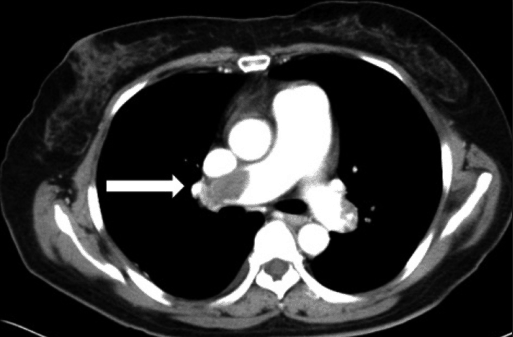

CT scan of pulmonary embolus resulting from the migration of a fat embolism to the lung.

Fat embolism is a phenomenon where fat particles get inadvertently deposited into regional vessels that then travel into organs, obstructing the flow of blood to that region; if the blood flow is obstructed to the lungs, termed a pulmonary embolus, death may occur.